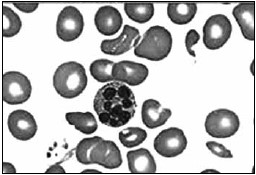

Uma das principais ameaças à saúde infantil é a desnutrição aguda grave. De acordo com a Organização Mundial da Saúde (OMS), cerca de 45% das mortes de crianças menores de cinco anos estão relacionadas com a desnutrição, acometendo, principalmente, países de baixa e média rendas. A seguir, encontra-se o resultado de uma eletroforese de proteínas e lâmina de esfregaço de sangue de uma criança 4 anos, que é de família de piaçabeiros, comunidade tradicional da Amazônia. Os dois resultados apontam, respectivamente, os seguintes diagnósticos e quadro de desnutrição da criança:

Figura 1

Figura 2

(Laudo e imagem cedidos pelo Laboratório de Análises Clínicas do Centro Universitário FMABC)